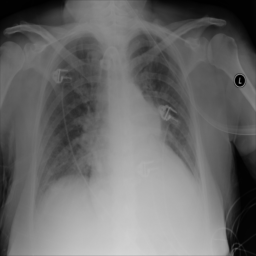

Figure 6: Examples of normal (left) and anomaly (right) images of H&E-stained lymph node of Camelyon16 challenge [3] (top) and chest X-rays of NIH dataset [4] (bottom). We also showed the predicted anomaly score by the proposed method. The higher the score, the more likely to be an anomaly. Notice how the proposed method spots even the borderline cases.

We illustrate the predictions of our model in Figure 6.

Anomaly Detection on Chest X-Rays

Chest X-ray is one of the most common examinations for diagnosing various lung diseases. We considered the task of the recognition of fourteen findings, such as Atelectasis or Cardiomegaly, on the chest X-rays in the NIH dataset (ChestX-ray14 dataset) [4] (Figure 2). Searching abnormalities on a chest x-ray is challenging even for an experienced radiologist since abnormality may occupy only a small region of lungs, or be almost invisible. The dataset consists of 112,120 frontal-view images of 30,805 unique patients: 86523 for training, 25595 for evaluation. We split the dataset into two sub-datasets having only posteroanterior (PA) or anteroposterior (AP) projections, because organs on them look differently. We tried different preprocessing during the hyperparameter search: rescaling to 256x256, 128x128, and 64x64 and histogram equalization, central crop (3/4 of the image size) to delete “noisy” borders. We considered images without any disease marker as “normal” and used them for training. Abnormal images for hyperparameter searching comprised of the training images of the most frequent disease (‘Infiltration’) out of fourteen possibilities. We also evaluated model on subset containing “clearer” normal/abnormal cases (provided by  [22]). This subset consists of 4261 normal images for training, 849 normal and 857 abnormal images for validation, and 677 normal and 677 abnormal images for testing.